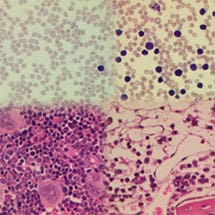

In pregnant mice which were genetically altered not to have these two defences, the equivalent of a single binge drinking session of alcohol caused catastrophic damage to the foetus. Not only did alcohol damage the foetus, but in the adult modified mice, this alcohol consumption damaged blood stem cells, obliterating the production of blood.

The study highlights how two groups who have inherited failures of the natural control mechanisms are particularly at risk of severe DNA damage from alcohol. Individuals with a rare disease called Fanconi Anaemia, which affects around 20,000 people worldwide, do not have the enzymes which repair DNA and are likely to be very sensitive to acetaldehyde. This could explain why such people are highly susceptible to both blood disorders and cancer. More commonly, around 500 million people from South East Asia with a condition called the ‘Asian alcohol flushing mutation’ have a greatly reduced capacity to break down acetaldehyde. This research suggests that these individuals may be susceptible to lifelong DNA damage and could explain why alcohol consumption greatly increases their risk of gullet cancer.